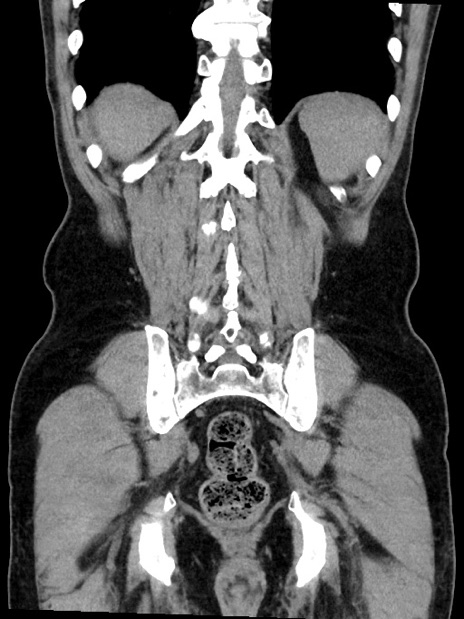

症例35(冠状断像)

【症例】70歳代 男性

【主訴】腹部膨満、嘔吐

【現病歴】昨日より腹部膨満感出現。本日増悪し、仙痛出現。嘔吐あり、受診。

【既往歴】糖尿病、胆摘後

【身体所見】BP 149/80mmHg、HR 74/min、BT 35.9℃、腹部:膨満、軟、圧痛なし。腸雑音減弱あり。上腹部正中切開瘢痕あり。

【データ】WBC 13500、CRP 1.72